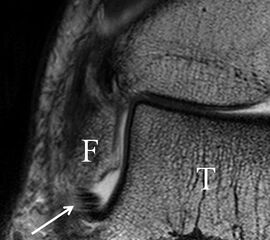

Physiologische Bandlücke (Pfeil)

Abbildung 9b

Zu Fehlinterpretationen eines intakten LFTA führt unter Umständen das unmittelbar kaudal des LFTA parallel verlaufende Ligamentum talocalcaneum laterale (Abb. 9 a). Dieses kann bei Verwendung von Schichtdicken um die 3 mm trotz Ruptur des LFTA durch Volumenteileffekte mit Anschnittsphänomenen einen intakten Bandverlauf vortäuschen.

Eine Ursache der falschen Diagnose einer LFTA-Ruptur ist die Fehlinterpretation der physiologische Bandlücke zwischen dem LFTA und der vorderen Syndesmose als traumatischer Banddefekt (Abb. 9 b).

Die Interpretation pathologischer Veränderungen sollte daher immer multiplanar unter Verwendung möglichst dünner Schichtdicken und hoher Ortsauflösungen erfolgen, um Fehldiagnosen zu vermeiden.